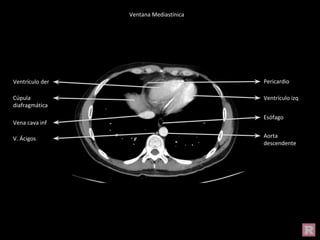

Cúpula

diafragmática

Ventrículo izq

Ventrículo der

Esófago

V. Ácigos

Vena cava inf

Aorta

descendente

Pericardio

Ventana Mediastínica

Cúpula diafragmática